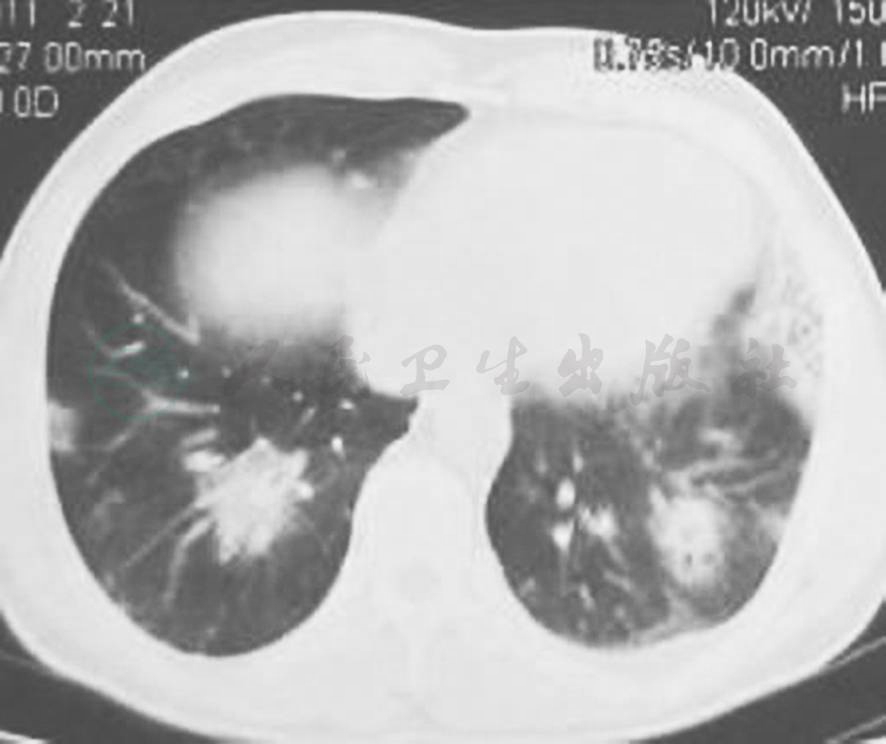

图3 胸部CT表现(2011-09-01)

胸部CT显示双肺阴影较前吸收,胸腔积液有减少